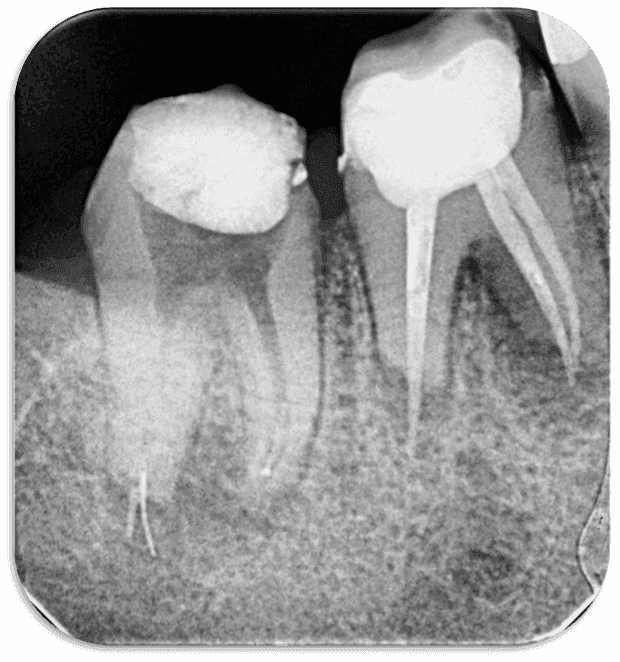

Daha sonra kontrol röntgeni alındı ve eğenin konumu tespit edildi (RESİM 4).

RESİM 4: Kırık eğenin ve taşkın gutanın kök ucundan apikale ilerlediği tespit edildi

İlk seans kanallara kalsin yerleştirildi ve hastadan alınan tomografi incelendi. Yapılan 3 boyutlu değerlendirmede kök ucundaki lezyonlu alanın kemikle çevrili olduğu, alt kısımdaki mandibular kanalla ilişkisinin olmadığı tespit edildi ve tedaviye cerrahi olmadan ortograd yöntemle devam edilmesi kararı alındı (RESİM 5).

RESİM 5: Mandibular kanal ve taşkın eğenin olduğu bölge